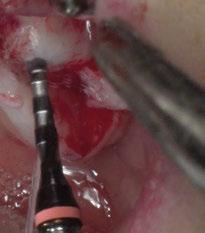

2. Fase quirúrgica inicial

En una primera fase quirúrgica, bajo sedación consciente y anestesia infiltrativa Articaína + epinefrina

40/0,01 mg/ml Ultracain®, 5 carpules en vestibular y palatino de la arcada superior, se realizó la exodoncia de la pieza 27 y la elevación sinusal bilateral. Se procedió a la elevación de los colgajos mucoperiósticos de espesor total y se posicionó la férula de

cirugía digitalmente guiada, pudiendo así marcar la forma de las ventanas de acceso con un lápiz estéril. En este caso en particular, podemos observar cómo pudimos realizar una doble ventana de acceso, evitando, de esta manera, el tabique presente. A continuación, se retiró la férula y se continuó con el procedimiento quirúrgico de realización de las ventanas de acceso mediante pieza

Figura 5. Encerado digital del caso.

Figura 10. Ventanas realizadas mediante pieza de mano y fresa de bola de diamante.

Figura 9. Marcación de las ventanas para la elevación sinusal.

Figura 11. Posicionamiento de membrana reabsorvible y chinchetas tras la elevación sinusal.

Figura 12. Ortopantomografía tras la elevación sinusal. Figura 13. Imagen CBCT tras la elevación sinusal.

de mano y fresa de bola de tungsteno y diamante. Se realizó el relleno mediante aloinjerto cortical Puros Zimvie® y se sellaron las ventanas de acceso mediante membranas reabsorvibles Copios Zimvie® fijadas con chinchetas por vestibular. Finalmente, se reposicionaron los colgajos y se suturó la parte crestal con sutura Supramid® 4/0 y la descarga con PGA® 5/0 (Figuras 8-13).